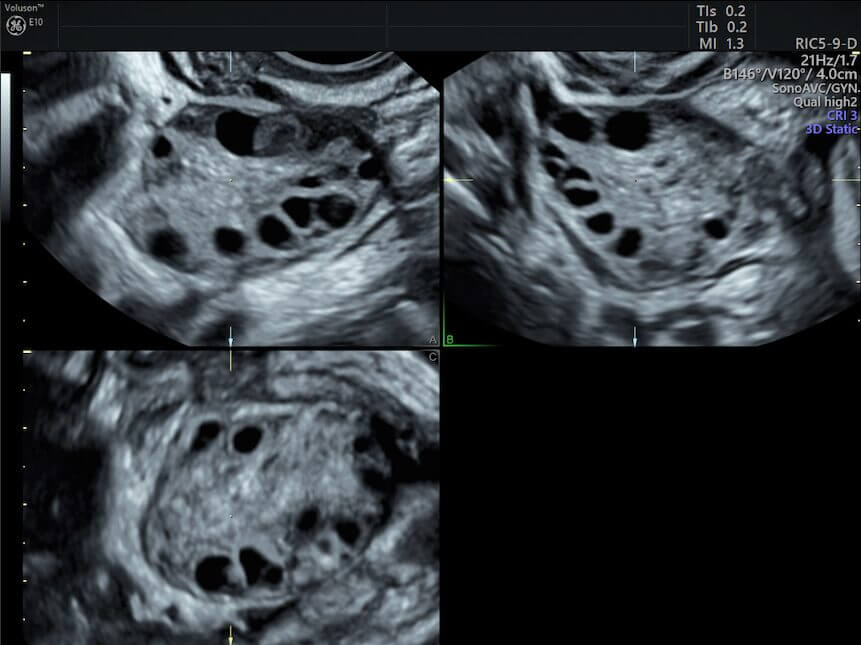

تعاني نسبة كبيرة من النساء من متلازمة تكيس المبايض أو ما يُعرف بـ متلازمة تكيس المبايض، وهي من أكثر الأسباب شيوعًا لتأخر الحمل. في هذه الحالة، لا تنضج البويضات بشكل طبيعي، مما يمنع حدوث التبويض المنتظم.

هنا تظهر قوة فيمارا، حيث أثبتت الدراسات أنها أكثر فعالية من بعض الأدوية التقليدية في تحفيز التبويض لدى مريضات التكيس. نحن نلاحظ في التجارب الواقعية أن:

نسبة حدوث التبويض ترتفع بشكل ملحوظ.

تقل احتمالية فرط تنشيط المبايض مقارنة ببعض الأدوية الأخرى.

هذا يجعل فيمارا خيارًا آمنًا وفعالًا في حالات التكيس.

تحسن واضح في التبويض عند متابعة السونار.

الكثير من النساء يروين أن أول دورة علاجية كانت مليئة بالتوتر، لكن مع رؤية البويضة تكبر على شاشة السونار، يبدأ الأمل يكبر معها. حجم البويضة عندما يصل إلى 18–22 ملم يكون مؤشرًا قويًا على قرب التبويض، وهنا تتجدد المشاعر ويبدأ العد التنازلي لأجمل خبر قد يغير الحياة بالكامل.

ظهور بويضات بحجم مناسب في السونار.

أما الاطمئنان فيبدأ عندما نرى استجابة واضحة في السونار، وعندما تتحسن الدورة الشهرية، وعندما يخبرنا الطبيب أن حجم البويضة ممتاز وأن بطانة الرحم مناسبة. هذه مؤشرات قوية أننا نسير في الطريق الصحيح.